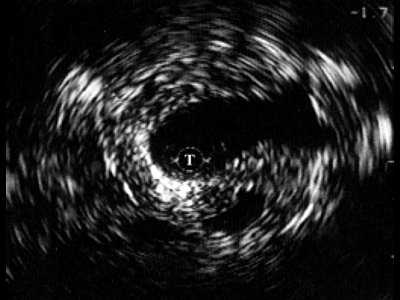

Четко визуализируются патологические образования в паренхиме (рис. 4). В зоне стриктуры мочеиспускательного канала определяется различной протяженности и глубины фиброзная ткань в виде гиперэхогенных участков.

Рис. 4. Эхограмма простатического отдела уретры.